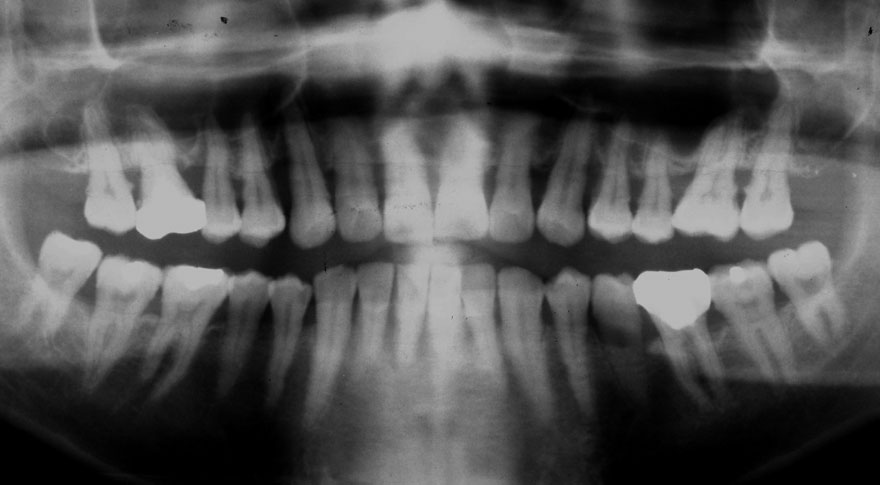

初診時 42歳 男性 平均歯槽骨喪失量:5.30mm

22年後 64歳

平均歯槽骨喪失量:5.554mm

22年間喪失量:-0.24mm

年間喪失速度:-0.01mm

(ケア頻度:1.07ヵ月ごと)